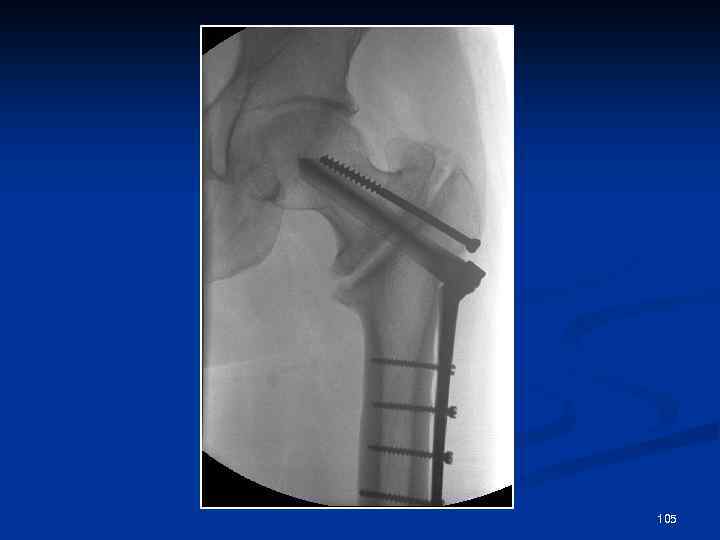

Патологическое заживление переломов Неправильно сросшиеся переломы Посттравматические синостозы Избыточная костная мозоль Асептический некроз (в т. ч. болезнь Кюммеляпосттравматический некроз тела позвонка) Несросшийся перелом Ложный сустав Неоартроз 103

104

105